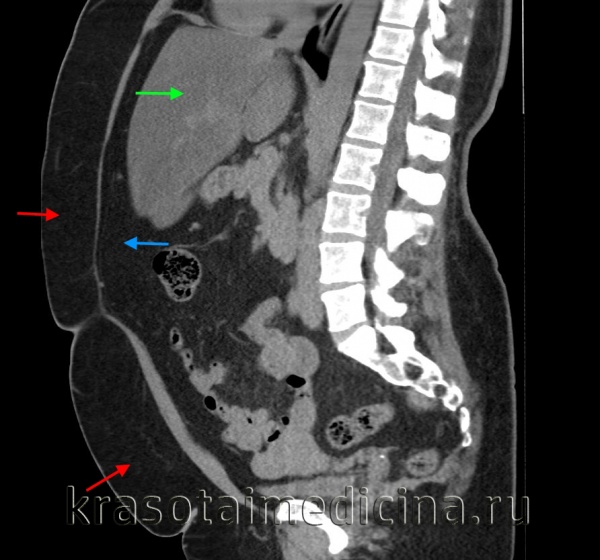

КТ ОБП. Избыточное количество подкожной жировой клетчатки живота (красная стрелка), висцеральной клетчатки (синяя стрелка), жировой гепатоз (зеленая стрелка).